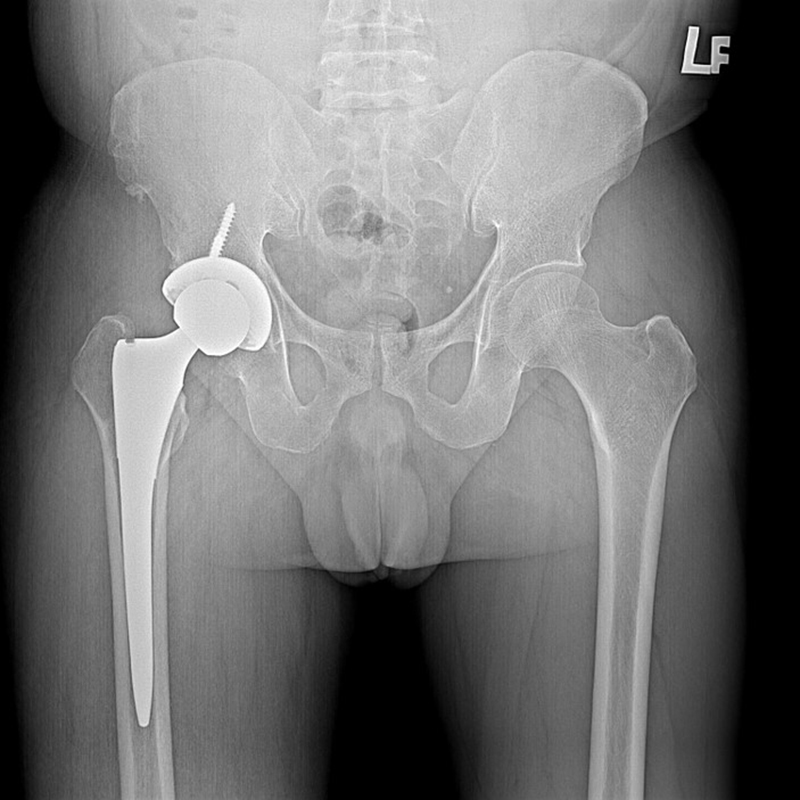

傳統髖關節置換 首頁 案例分享 髖關節手術 傳統髖關節置換 54歲蔡先生退化性關節炎 術前 術後 張女士 51歲 退化性關節炎(DDH先天發育不全 CROWE TYPE 2) 術前 術後 38歲林先生 退化性關節炎 術前 術後 72歲謝女士 退化性關節炎 術前 術後 71歲 謬女士 骨股頭壞死 術前 術後 50歲 郭先生骨股頭壞死 術前 術後 80歲 盧先生骨股頭壞死 術前 術後 林先生 37歲 術前 術後 邱女士 51歲 術前 術後 張女士 50歲 術前 術後